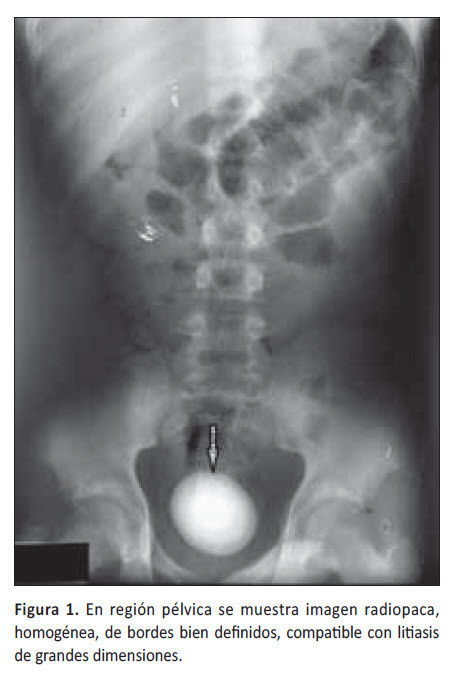

RADIOGRAFIA SIMPLE

Como apoyo diagnostico para patologia uretral, estenosis uretra. No como examen de tamizaje Sindrome de tracto inferior mas estos antecedentes (ITS, intrumentalizacion, traumas de uretra),  se sospecha lesion estenotica de la uretra. Se puede evaluar la distancia de la lesion estenotica, nivel de inicio y termino. A diferencia de la cistoscopia en el que con una camra con fuente de luz se entra por la uretra llegando a la vejiga. Muy invasivo. Radiografia simple con contraste: Se aplica medio de contraste en la vejiga, por puncion o con sonda, pudiendo evaluar el trauma, uropatia obstructiva bja, o zona que no este distendiendose adecuadamente, rotura, lesion de vejiga. No sirve para ver litiasis, es poco sensible pero muy especifica. Existen piedras radioopacas y radiolucidas

La radiografia entiempo real sirve para apoyo en procedimiento quirirgicos y diagnsoticos. Litiotripsia extracorporea: Un calculo ubicado en la zona del ureter proximal o riñon, que mida <2 cm y que sea radiopoca se puede fragmentar mediante ondas de choque. Para esto se utlizan radiografias en tiempo real. Uretrocistografia (vejiga mas uretra): Tambien se utiliza la radiografia cuando ya se inyecto el contraste.